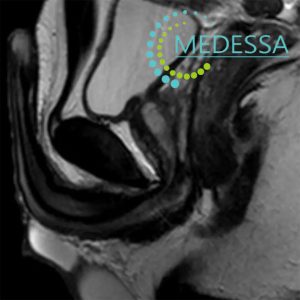

Magnetic Resonance Imaging (MRI) of internal organs is a modern non-invasive diagnostic method that allows detailed visualization of organs, tissues, and anatomical structures without surgery or radiation exposure.

Due to its high diagnostic accuracy, MRI can detect even minor tissue changes, which is crucial for the early identification of tumors, inflammatory processes, and other abnormalities.

Pelvic MRI

For men:

- Urinary disorders.

- Pelvic or perineal pain.

- Suspected prostate diseases.

- Inflammatory urogenital conditions.

Rectal MRI

- Blood in stool or bowel habit changes.

- Anal or rectal discomfort.

- Suspected tumors or polyps.

- Cancer staging and assessment.

- Preoperative planning.